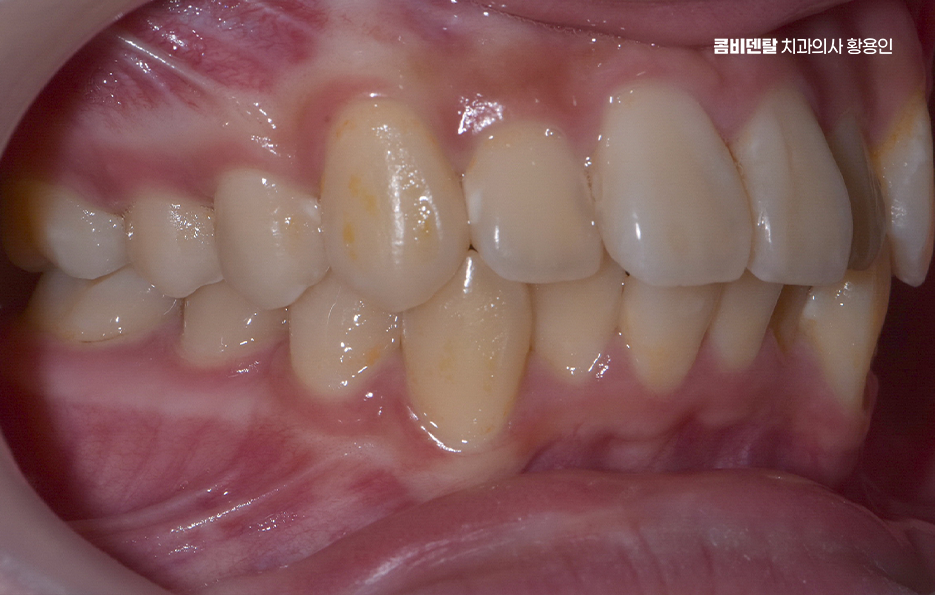

특히 교합이 틀어진 상태에서는 특정 치아에만 씹는 힘이 과도하게 실리게 되는데 이로 인해 일부 치아는 빠르게 마모되거나 깨지게 되고, 반대로 거의 사용되지 않는 치아는 치주 조직이 약해져서 잇몸 퇴축이나 치주염이 생길 확률도 높아지는 거예요. 그리고 치열이 고르지 않은 상태에서는 양치질을 꼼꼼히 해도 치간이나 치아 뒷면에 음식물과 세균이 남기 쉬워서 충치 발생률도 높아지는 건 당연한 것이며 결국 부정교합은 기능적인 저작 문제, 치아의 수명 단축, 잇몸 질환이라는 복합적인 문제로 이어지게 될 수 있어요

부정교합 교정 안하면 또 부정교합이 얼굴형이나 턱관절에 끼치는 영향도 결코 가볍게 봐선 안 되는 부분인데 치아가 가지런하지 않으면 턱의 움직임도 비대칭적으로 진행되기 쉽고 이로 인해 한쪽 턱이 과도하게 발달하거나, 얼굴 한쪽이 더 튀어나와 보이거나, 심한 경우 턱관절에서 ‘딱딱’ 소리가 나거나 입이 잘 벌어지지 않는 턱관절 장애로 발전하는 경우도 있어요

그렇다면 이런 부정교합 문제를 해결하기 위해선 어떤 방식으로 치료계획을 세워야 하느냐가 중요한데 첫 번째 단계는 정밀한 진단과 분석으로 단순히 눈으로 보기엔 어느정도 가지런해 보여도 실제로는 턱의 중심선이 틀어져 있거나, 치아의 경사가 비정상적으로 되어 있을 수 있기 때문에 파노라마 X-ray, 세팔로, 구강 스캐너, 3D CT 등을 통해 턱의 구조, 치아 배열, 뼈 상태 등을 면밀히 분석해야 정확한 치료계획이 세워지는 거예요.